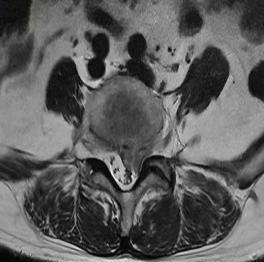

• 不同入路脊柱内镜手术治疗L4/5节段脱垂型腰椎间盘突出症的疗效比较

摘要:目的 观察经椎间孔入路内镜下腰椎间盘切除术(TELD)和经椎板间入路内镜下腰椎间盘摘除术(IELD)治疗L4/5节段脱垂型腰椎间盘突出症(LDH)的临床疗效。方法 回顾性分析2020年11月-2022年11月该院采用脊柱内镜手术治疗的75例L4/5节段脱垂型LDH患者的临床资料。根据手术入路的不同,将患者分为TELD组(53例)和IELD组(22例)。比较两组患者的手术情况和术后疗效。结果 与TELD组比较,IELD组的手术时间明显缩短,术中透视次数明显减少,差异均有统计学意义(P < 0.05);两组患者住院时间和并发症发生率比较,差异均无统计学意义(P > 0.05)。所有患者术后均获得12~19个月的随访。两组患者末次随访时的视觉模拟评分法(VAS)评分和Oswestry功能障碍指数(ODI)明显低于术前,且IELD组明显低于TELD组,差异均有统计学意义(P < 0.05)。按照突出物和神经根的不同位置进一步分析,两组肩上型患者(TELD组10例,IELD组6例)末次随访时的VAS评分和ODI明显低于术前,且IELD组末次随访时的VAS评分明显低于TELD组,差异均有统计学意义(P < 0.05);两组腋下型患者(TELD组8例,IELD组16例)末次随访时的VAS评分和ODI明显低于术前,且IELD组明显低于TELD组,差异均有统计学意义(P < 0.05);35例肩前型患者经TELD术后,末次随访时的VAS评分和ODI明显低于术前,差异有统计学意义(P < 0.05)。按照突出物的不同Lee分区进一步分析,两组Lee Ⅲ区患者(TELD组44例,IELD组10例)末次随访时的VAS评分和ODI明显低于术前,且IELD组的ODI明显低于TELD组,差异均有统计学意义(P < 0.05);两组Lee Ⅳ区患者(TELD组9例,IELD组12例)末次随访时的VAS评分和ODI明显低于术前,且IELD组明显低于TELD组,差异均有统计学意义(P < 0.05)。结论 采用TELD和IELD治疗L4/5节段脱垂型LDH,均可获得较满意的减压效果,但IELD的手术时间相对较短,X线透视次数较少,且对肩上型、腋下型、Lee Ⅲ区和Lee Ⅳ区的减压效果更有优势。